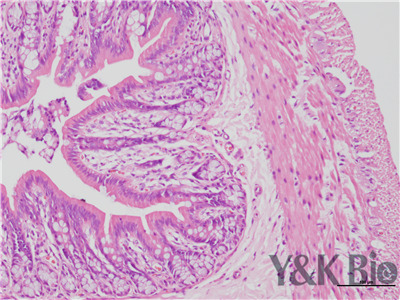

病理技术服务中HE染色法,学名苏木精-伊红染色,在法重庆石蜡切片技术里是经常用的染色法之一。石蜡切片常用于观察正常细胞组织的形态结构,是病理学用以研究、观察及判断细胞组织形态变化的主要方法。苏木精染液是碱性的 ,主要使细胞核内的染色质与胞质内的核糖体着紫蓝色 ;伊红为酸性的染料 ,主要使细胞质和细胞外基质中的成分着红色。HE染色法是组织学、胚胎、病理学教学与科研中基本、使用广泛的技术方法。

HE染色中要注意细胞核的分化程度,注意苏木素和伊红的效价,及时更换染液,一般实验周期为15个工作日。